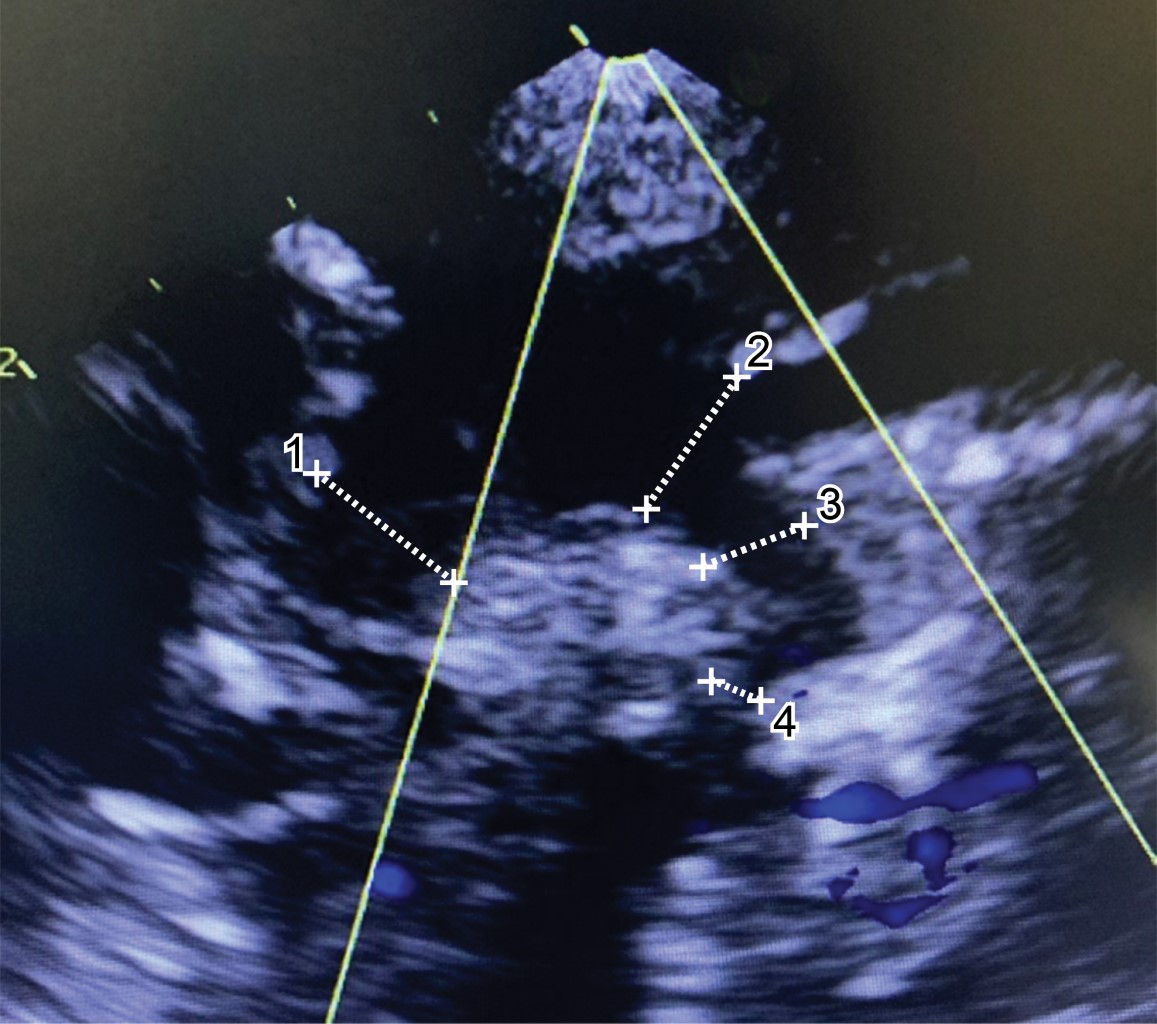

Presentamos el caso de un recién nacido de embarazo gemelar monocoriónico, producto de la cuarta gestación y nacimiento a las 35.2 semanas. La indicación de la cesárea fue por alteración en el crecimiento intrauterino del gemelo 2 (peso estimado por USG un día previo; gemelo 1: 2.4 kg, gemelo 2: 1.7 kg) y flujos placentarios normales. Se obtiene a recién nacido por cesárea, gemelo 2 con llanto vigoroso y esfuerzo respiratorio adecuado. Valoración Apgar 8-8, peso 1,700 gramos, escala de Silverman 2 y frecuencia respiratoria de 65 respiraciones por minuto, manejado con oxígeno indirecto con casco cefálico a 40% y 5 L/min. Inicialmente asintomático con pulsos presentes las primeras 12 horas de vida extrauterina. Posteriormente muestra soplo sistólico en mesocardio con irradiación al dorso. Los pulsos arteriales se encontraban presentes en las cuatro extremidades, aunque los femorales discrepan de los radiales en intensidad y amplitud. El ecocardiograma inicial mostró coartación aórtica crítica (CoAo) con gradiente medio de 52 mmHg, hipoplasia del arco aórtico y ductus arterioso permeable grande (Figura 1). El abordaje inicial fue la infusión de alprostadil (Alisitin 500®) a una dosis 0.1 µg/kg/min, retiro del aporte de oxígeno y solicitud de angiotomografía de aorta (previa valoración de una función renal normal) donde se confirma el diagnóstico con descripción de coartación aórtica con diámetros: ascendente 6 mm, transversal 5 mm, descendente 4 mm y zona de coartación 2 mm (Figura 2).

Figura 1